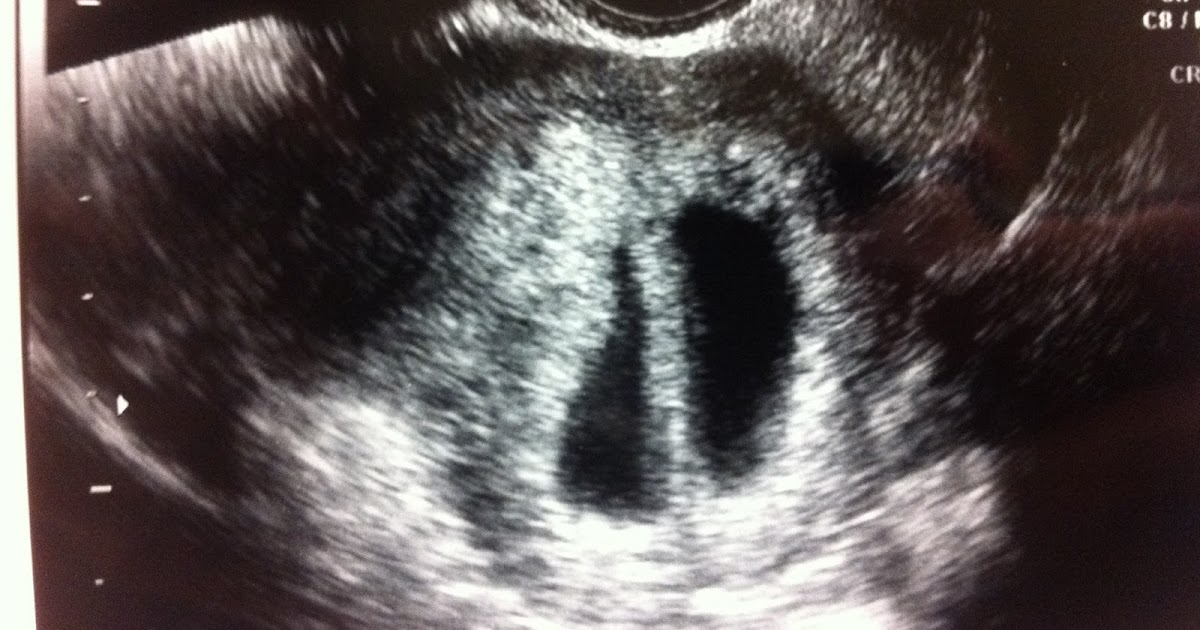

Twin Parenting Twin ultrasound 8 weeks How Soon Can An Ultrasound Detect Twin Pregnancy An ultrasound will usually be able to detect a twin pregnancy early on, but sometimes a twin pregnancy can be detected even earlier through a pregnancy blood test. in this review, we summarise the latest evidence relating to ultrasound. Typically, you'll find out if you're having twins during a first trimester ultrasound. complicated monochorionic twins should be examined. How Soon Can An Ultrasound Detect Twin Pregnancy.